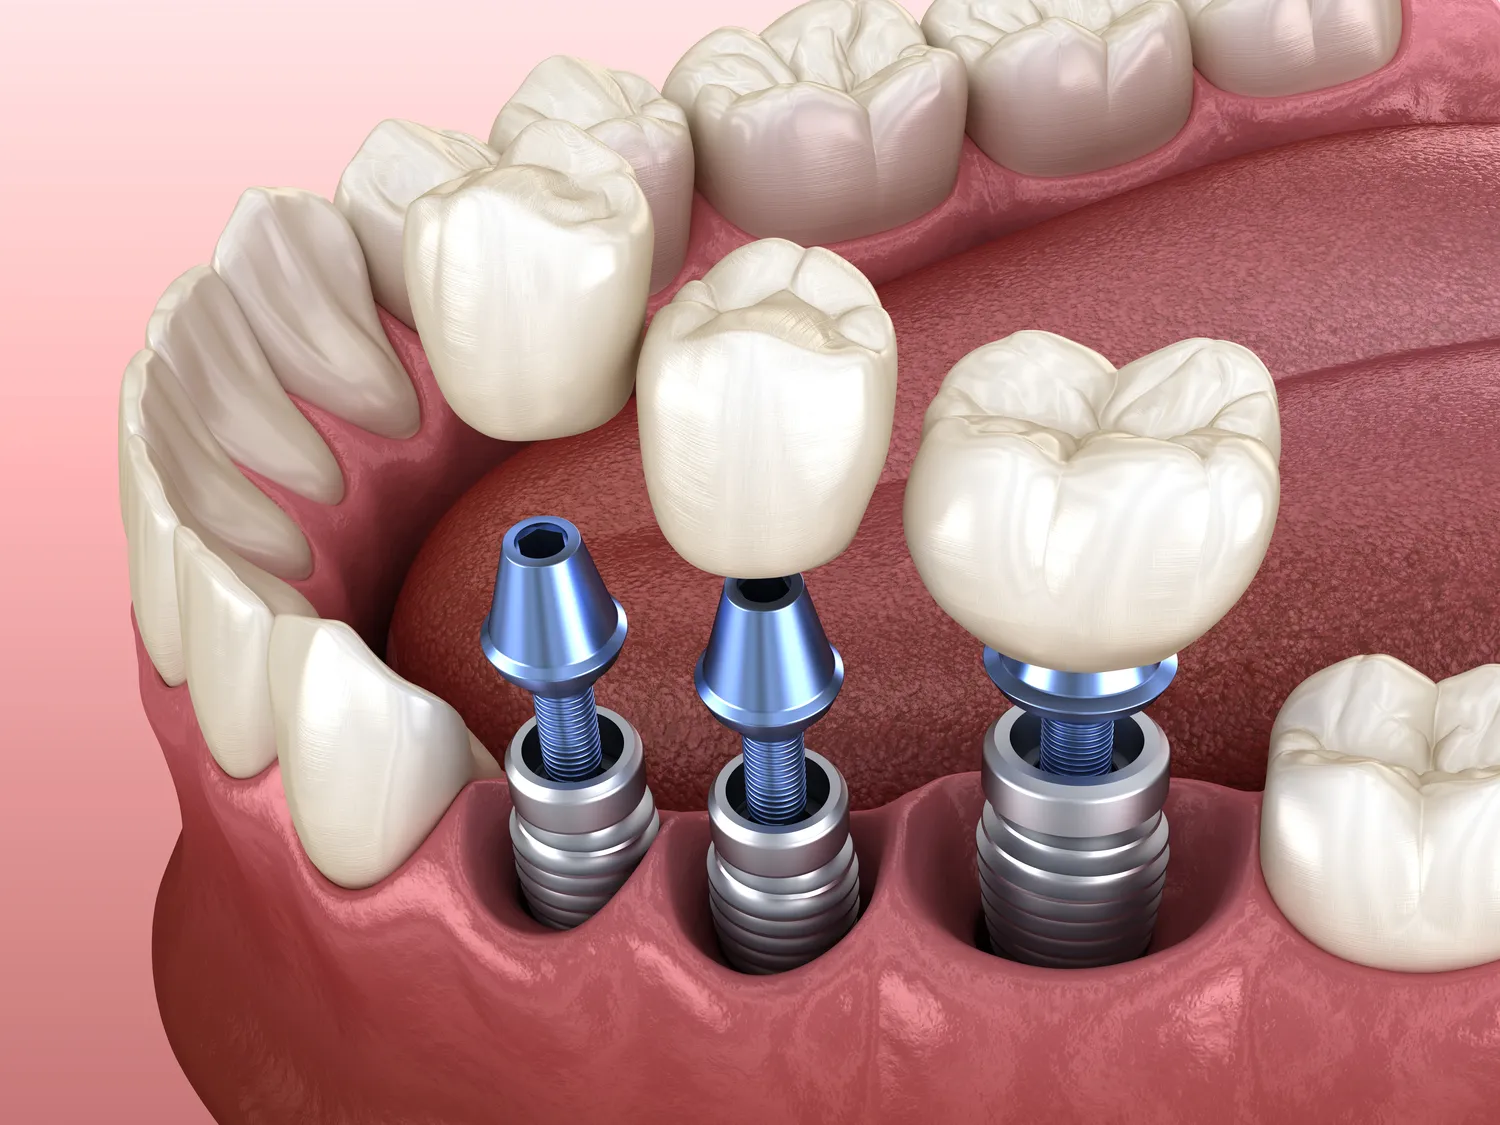

Rynek implantów stomatologicznych oferuje różnorodność rozwiązań, dostosowanych do indywidualnych potrzeb pacjentów oraz specyfiki planowanego leczenia. Najczęściej stosowane są implanty śródkostne, które stanowią najbardziej powszechne i najszerzej badane rozwiązanie. Są one zazwyczaj w kształcie stożka lub cylindra z gwintem, co ułatwia ich stabilizację w kości. W zależności od potrzebnej stabilizacji i budowy kości, mogą mieć różne średnice i długości. Poza implantami śródkostnymi, które są umieszczane bezpośrednio w tkance kostnej, istnieją również implanty podokostnowe. Są one stosowane w przypadkach, gdy kość jest zbyt niska lub zbyt słaba, aby umożliwić wszczepienie implantu śródkostnego. Implant podokostnowy składa się z metalowej siatki, która jest dopasowywana do powierzchni kości, a następnie cementowana. Implanty te stanowią alternatywę, choć rzadziej stosowaną ze względu na większą złożoność zabiegu i potencjalnie dłuższy okres gojenia.

- Implanty śródkostne wszczepiane bezpośrednio w kość, stanowiące sztuczny korzeń zęba.

- Implanty podokostnowe stosowane przy znacznych zanikach kości, montowane na jej powierzchni.

Sam zabieg wszczepienia implantu zazwyczaj odbywa się w znieczuleniu miejscowym, co sprawia, że jest on komfortowy dla pacjenta. Po odpowiednim znieczuleniu obszaru zabiegowego, chirurg wykonuje niewielkie nacięcie dziąsła, aby odsłonić kość. Następnie, przy użyciu specjalistycznych wierteł o stopniowo zwiększającej się średnicy, przygotowywane jest łoże dla implantu. Precyzja jest tutaj kluczowa, aby implant został umieszczony w optymalnej pozycji, zapewniającej stabilność i prawidłowe obciążenie przyszłą odbudową protetyczną. Po przygotowaniu łoża, implant jest delikatnie wkręcany w kość. W zależności od sytuacji klinicznej, po wszczepieniu implantu może zostać on przykryty śrubą gojącą, która formuje dziąsło wokół implantu, lub od razu może zostać zamontowana śruba nadbudowująca, która wystaje ponad poziom dziąsła. Cały zabieg, w zależności od liczby implantów i złożoności przypadku, może trwać od kilkudziesięciu minut do kilku godzin. Po zakończeniu zabiegu, miejsce wszczepienia jest zazwyczaj zaopatrywane szwami.

Po zabiegu implantacji następuje kluczowy okres osteointegracji, czyli proces zrastania się implantu z kością. Trwa on zazwyczaj od 3 do 6 miesięcy, a w niektórych przypadkach może być dłuższy. W tym czasie implant staje się integralną częścią kości, zapewniając mu stabilność i wytrzymałość porównywalną z naturalnym korzeniem zęba. W okresie gojenia niezwykle ważna jest odpowiednia higiena jamy ustnej, unikanie nadmiernego obciążania wszczepionego implantu oraz stosowanie się do zaleceń lekarza, w tym przyjmowanie przepisanych leków. Po zakończeniu osteointegracji, przystępuje się do etapu protetycznego, polegającego na wykonaniu i zamocowaniu na implancie docelowej odbudowy, takiej jak korona, most czy proteza. Ten etap również wymaga precyzji i współpracy pacjenta z technikiem dentystycznym oraz lekarzem protetykiem, aby uzyskać naturalny wygląd i pełną funkcjonalność uzupełnienia.